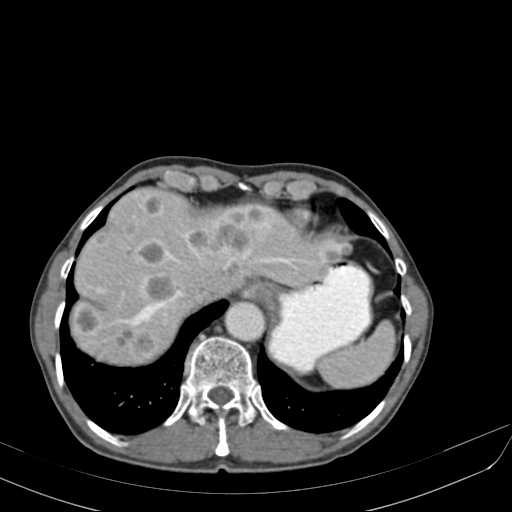

Existem algumas situações onde o paciente já apresenta um diagnóstico bem definido e o exame é solicitado para se avaliar a gravidade do quadro. Como, por exemplo, em uma paciente de 55 anos, do sexo feminino, com câncer de cólon recém-descoberto. Uma tomografia computadorizada de abdome é solicitada para avaliação do quadro.

A tomografia computadorizada demonstra múltiplos nódulos hepáticos difusos pelo fígado, compatíveis com metástases.

Este é um exemplo de como um exame de imagem pode ser solicitado para um paciente que, embora já tenha um diagnóstico bem definido, necessita de avaliação da extensão do acometimento de sua doença.